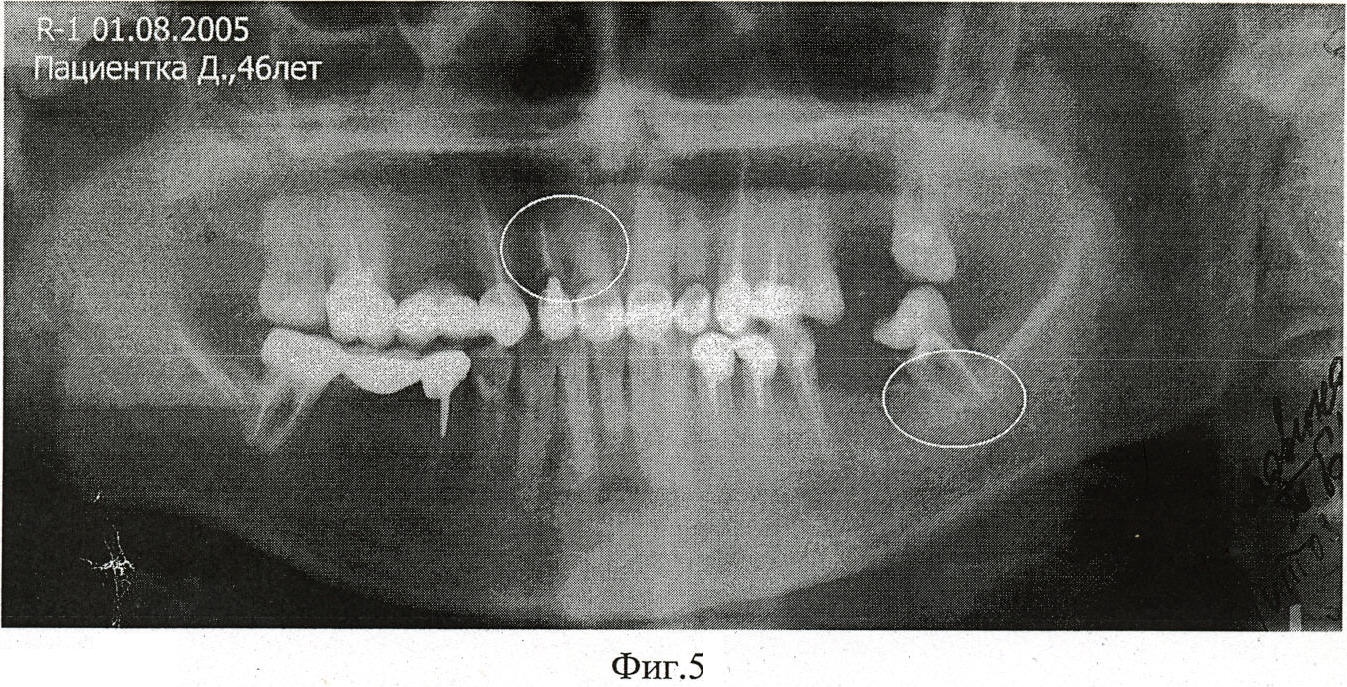

Фиг.5 – Рентгенограмма пациентки Д. перелом корня зуба до лечения.

Пациентка Д., 48 лет, поступила в клинику ИСЦ «НАНО-ДЕНТ» с диагнозом: периодонтит с переломом корня 11 зуба (см. Фиг.1).

По геометрии созданного канала в корне 11 зуба и в кости над 11 зубом подобрали нужный имплантат. Заявляемый материал ввели инъекцией (шприцем) в челюсть, в корне – костный канал 11 зуба, перед введением имплантата, затем ввели предварительно охлажденный имплантат, имеющий прямолинейную форму в плане.

Фиксировали имплантат в течение 10 с пальцами рук, при этом имплантат в костной ткани нагрелся до температуры тела пациента, (см. Фиг.6). Таким образом, при постоянной температуре тела (36-37)°С осуществилась надежная фиксация имплантата в челюсти.

На Фиг.7 – рентгенограмма пациентки Д. через 2,5 года после лечения с введеннием имплантата. Корень 11 зуба укреплен, гранулы никелид-титана-серебра сферически ориентированы вокруг имплантата с метаплазией периодонта в геторофазный буферный композит – периимплант, ориентированный по силовым линиям и выполняющий функцию демпфера во вновь образованной системе «Имплантат-Периимплант-Кость».